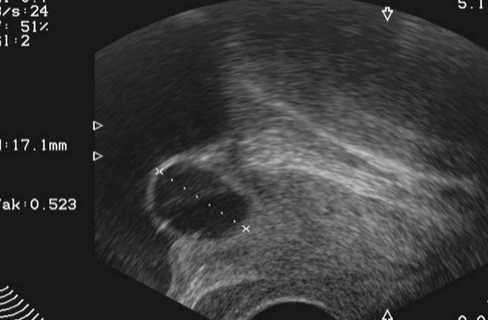

낭종이 클 경우, 미세 침습 수술이 선택될 수 있습니다. 이러한 수술은 초음파, 컴퓨터 토모그래피 (CT) 스캔, 자기 공명 영상 (MRI) 등의 가이드 하에 수행됩니다. 이 과정에서 의사는 작은 침을 통해 낭종으로 가는 길을 만들고, 그 후에 이 침을 통해 낭종에 들어가 액체를 배출합니다. 이렇게 하면 낭종의 크기가 줄어들고 증상이 완화됩니다.